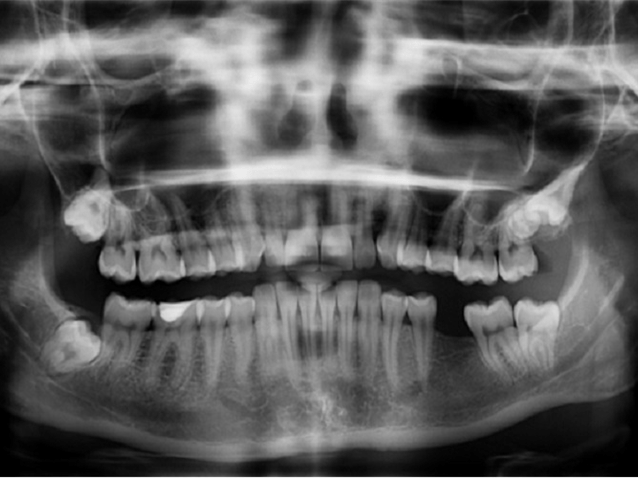

Cirurgiã-dentista do SESC - Serviço Social do Comércio tem direito a adicional de insalubridade pelo contato com amálgama dentário, composto de uma liga de limalha de prata e mercúrio líquido. O SESC havia recorrido da condenação, porém a 1ª turma do TST não conheceu o seu recurso contra decisão desfavorável do TRT da 4ª região/RS, mantendo, portanto, a condenação.

A reclamante reitera a pretensão de insalubridade em grau máximo. Argumenta que como cirurgiã-dentista mantinha contato com pacientes portadores de doenças infecto-contagiosas e manuseava mercúrio líquido contido na liga do amálgama dentário.

É comprovado nos autos que a reclamante mantinha contato com amálgama dentário, que se constitui por uma liga de limalha de prata e mercúrio líquido-. A teor do disposto no Anexo 11 da NR-15 da Portaria 3214/78, o perito do juízo esclareceu que o mercúrio manipulado pela autora é metálico, inorgânico e que, -para haver a caracterização da insalubridade, deveria ser monitorada quantitativamente a concentração de mercúrio (todas as formas exceto orgânicas) e, sendo ultrapassados os limites de tolerância legais (0,04 ppm), a mesma seria caracterizada- (fl. 237).

É relevante destacar os esclarecimentos do perito de que -o mercúrio inorgânico (metálico) utilizado no amálgama dentário é tóxico a micoorganismos tendo sido reportados efeitos tóxicos à exposição de 5 ug/l. Exposições com inalação aguda ao vapor de mercúrio pode ser seguida por dores de cabeça, dispnéia e até pneumonia intersticial que às vezes conduz à morte. A ingestão de compostos mercuriais, o cloreto de mercúrio em particular, causa gastroenterite ulcerativa e necrose aguda. O sistema nervos central é órgão crítico para a exposição a vapores de mercúrio. Exposições podem resultar em reações psicóticas caracterizadas por delírios, alucinações e tendências suicidas. A diminuição da velocidade da condução nervosa tem sido demonstrada na exposição de trabalhadores a vapor de mercúrio. Tanto o vapor de mercúrio metálico como os compostos de mercúrio implicam em dematite de contato. Exposições ao vapor de mercúrio podem causar a doença de -Kawasaki-. Em alguns estudos foram reportados efeitos no ciclo menstrual e no desenvolvimento de fetos. As publicações correntes de estudos epidemiológicos ainda deixam em aberto tais efeitos adversos. Recentemente tem havido intenso debate acerca da segurança dos amálgamas dentários e reivindicações tem sido feitas de que o mercúrio do amálgama pode trazer severos perigos à saúde. Há artigos descrevendo diferentes tipos de sintomas e sinais embora os resultados de alguns estudos epidemiológicos produzidos sejam ainda inconclusivos- (fl. 237).